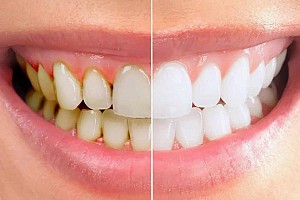

Hình ảnh trước và sau khi lấy cao răng

Để bảo vệ sức khỏe răng miệng tốt, bạn nên khám và lấy vôi răng định kỳ 6 tháng 1 lần. Ngoài ra, cũng nên chăm sóc sức khỏe răng miệng hằng ngày như: